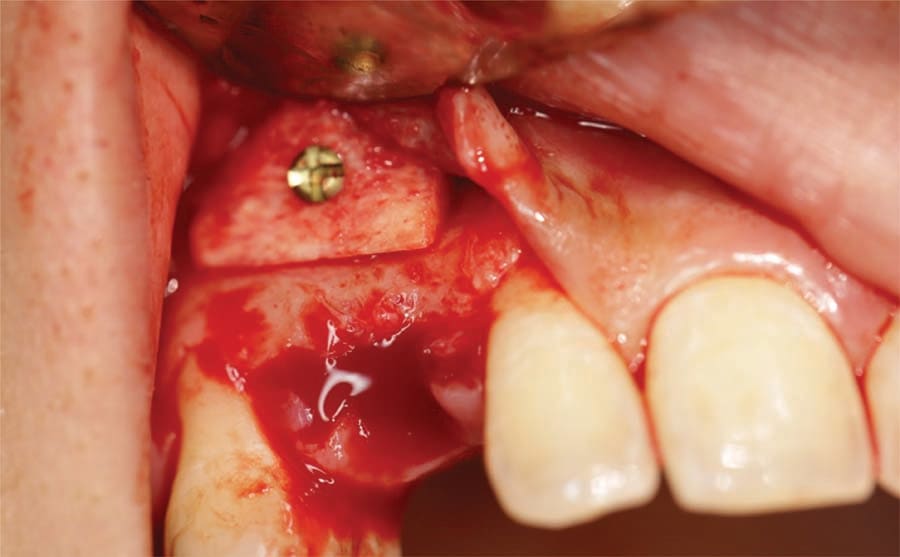

The patient presented for extraction of the deciduous canines and block grafting of the sites. Consent forms were reviewed with the patient and were signed. Local anesthetic was administered at the sites. Teeth C and I were extracted atraumatically, and a full-thickness mucoperiosteal flap was elevated at those sites (Figure 6). In this patient cortico-cancellous block grafts bilaterally were chosen (Puros® J-Block, ZimVie). The block of bone was contoured first on the cancellous alveolar side, with a football-shaped bone bur. The bone was placed in the recipient bed and was held firmly; the rest of the contouring was performed on the cortical side to allow the block to fit the site. Minimizing the thickness of the cortical bone also reduces the risk of dehiscence of the area. The cortical side was reduced significantly to allow adequate penetration of blood to allow integration and remodeling to native bone but leaving sufficient cortex to support adequate fixation. Next, using a 1.2-mm drill, the recipient site was thoroughly perforated to allow fresh bleeding and adequate penetration of the blood cells and growth factors into the graft. The graft then was firmly held against the recipient site, the 1.2-mm drill was used to place the screw hole, and a 1.2-by-10-mm screw was used to the secure the block graft into place (Figure 7). This was repeated at the left canine site (Figure 8). Particulate graft was not added so that the periosteum was in direct contact with the block to allow faster vascularization of the block graft. The periosteum underneath the flap was thoroughly scored and the flap was advanced to achieve tension-free primary closure and secured with 4-0 Vicryl sutures (Figure 9). The patient was seen for follow-up 1 week post-surgery.